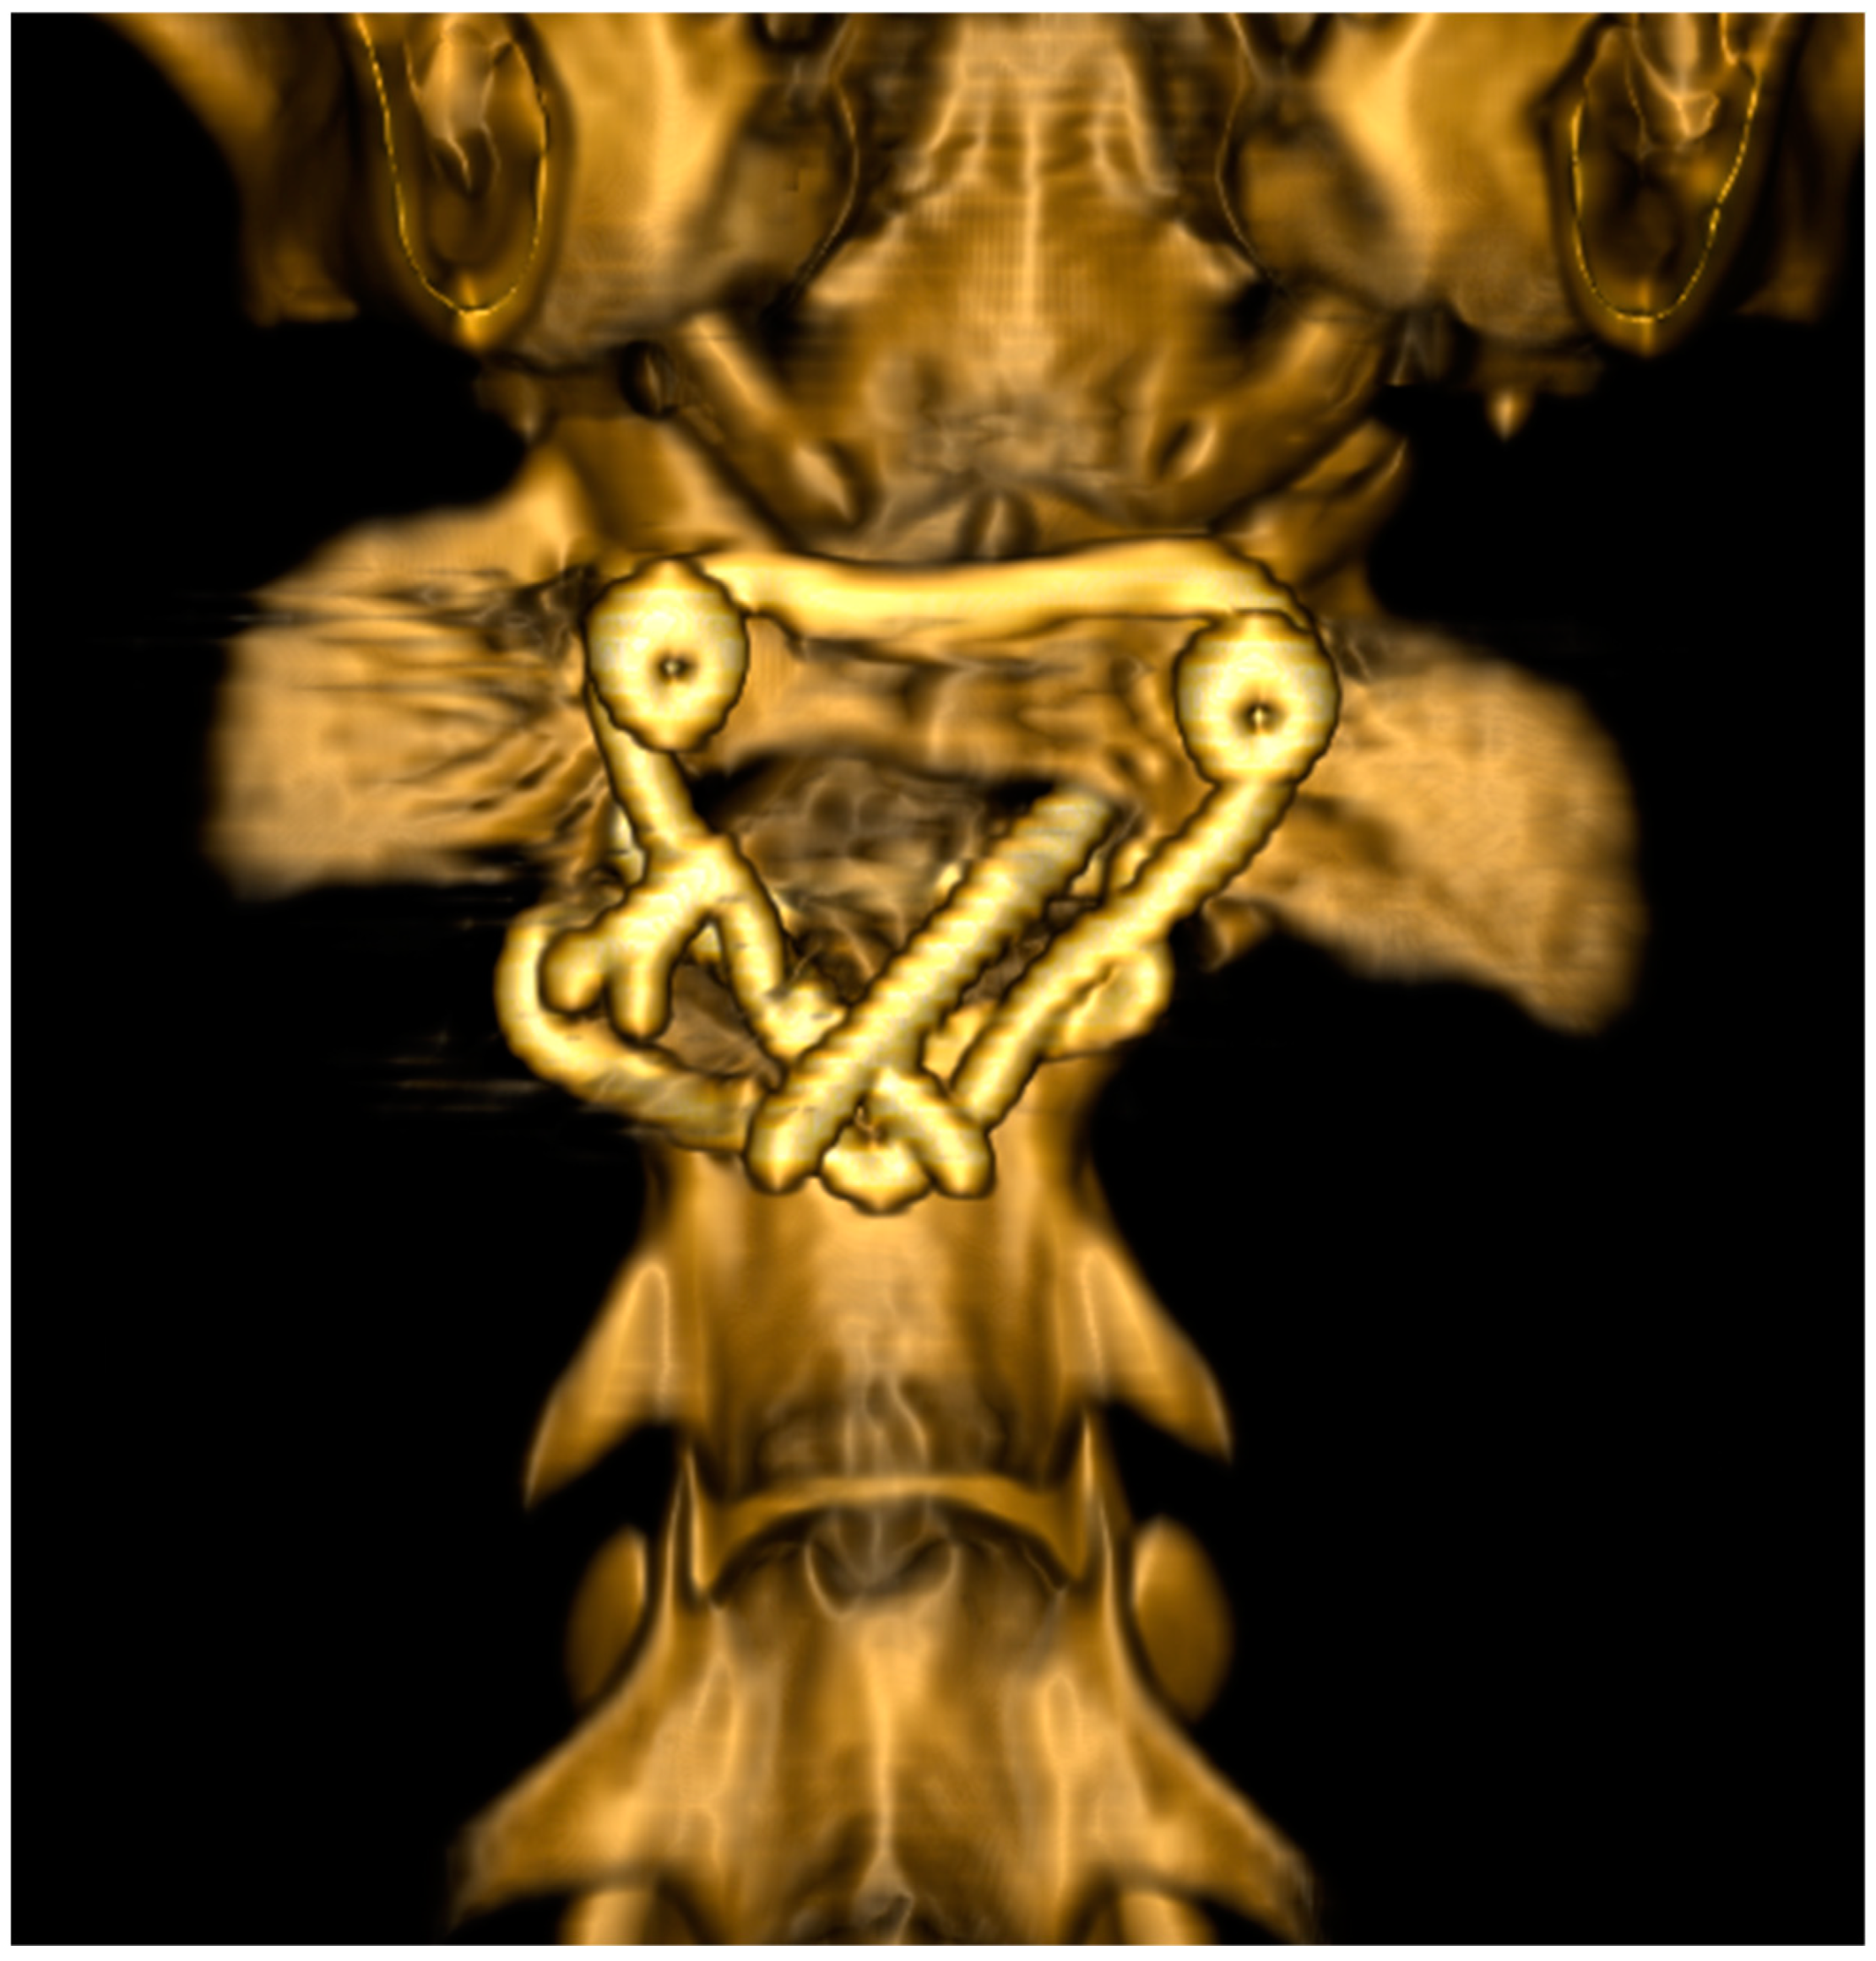

2.4.1. Radiographs

2.4.2. Computed Tomography